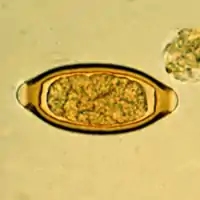

Egg of Trichuris trichiura